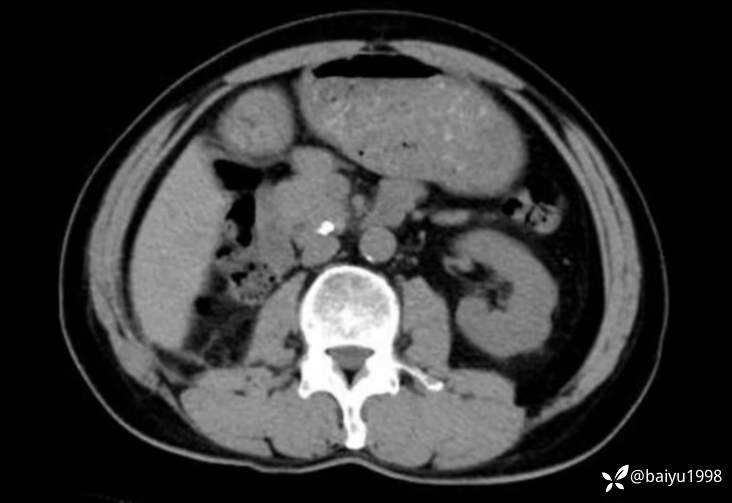

下午门诊看了一位老先生,外地给他做肾脏手术时发现了胰腺钙化,因此建议到我们长海医院来进行体外碎石和ERCP。我给他完善了MRCP和胰腺ct的检查,大家看看是否需要做进一步治疗